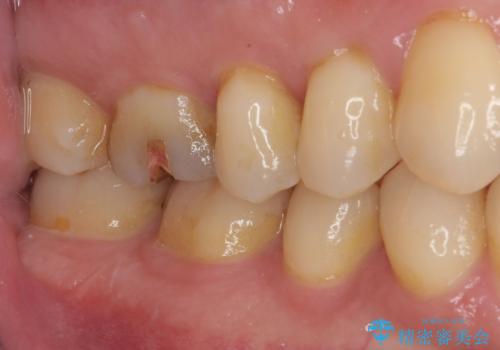

ゴールドは柔軟性があり、精密に加工できるため、歯とインレーのすき間が限りなく少ない状態で作成できます。これにより、虫歯の再発リスクを抑えることができます。

舌で触ると段差が気になる ゴールドインレー修復